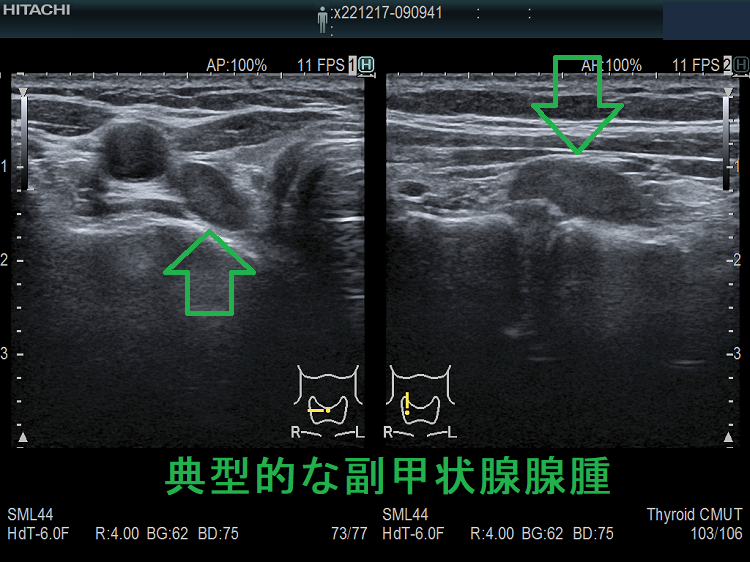

(➸)原因となる副甲状腺腺腫、副甲状腺癌、副甲状腺過形成をデジタルハイビジョン超音波診断装置で診断。エコーでは、甲状腺とのインピーダンスの違いにより、甲状腺-副甲状腺境界部に線状高エコーが生じます(右図の↓)。内部は中心血流を認め、リンパ節でないのが分かります。

ケース①

ケース② 右腕頭動脈分岐部上の副甲状腺腫

ケース②